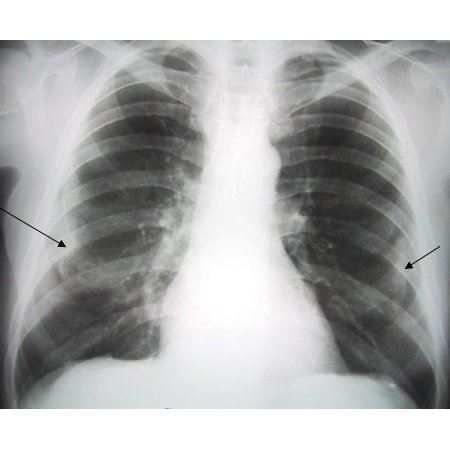

Asbestosis

Posterior-anterior view of the chest with "en face" pleural changes in the mid zones on the right and left (arrows)

From the personal collection of Kenneth D. Rosenman MD